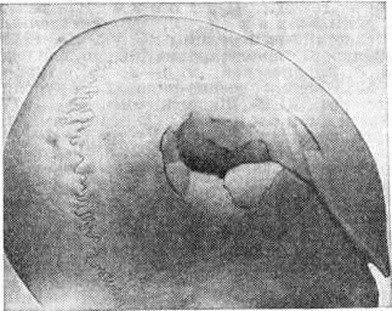

При точном сопоставлении отломков возможно прямое костное сращение с помощью интермедиарной костной мозоли, что именуют первичным костным сращением. Когда сращение отломков наступает после предварительного соединения их костно-хрящевой провизорной мозолью, на основе которой постепенно будет формироваться окончательная интермедиарная костная мозоль, говорят о вторичном костном сращении. Первичное костное сращение может произойти только в строго определённых условиях: при достаточном кровоснабжении отломков, точности их сопоставления, достаточности их обездвижения. Микрофотографии кости при первичном сращении в разные сроки консолидации представлены на рисунок 1 и 2.